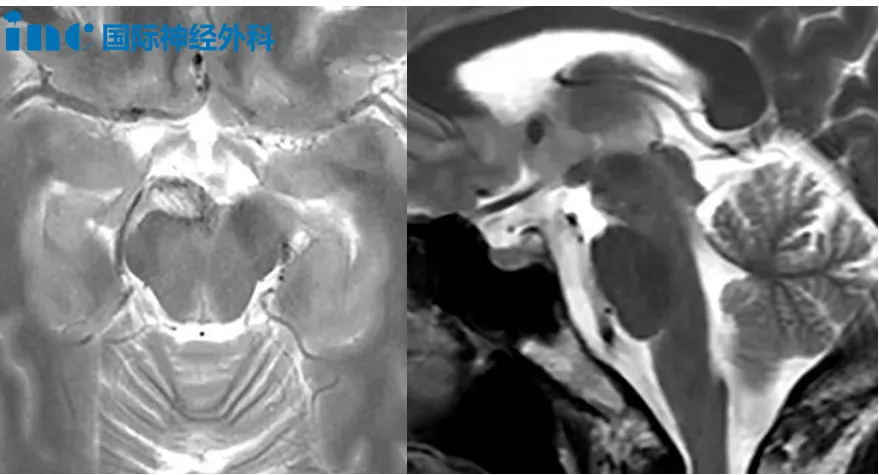

5岁男性患儿布布,2023年因行走不稳发现颅内占位,同年9月接受首次第四脑室肿瘤切除手术,术后病理诊断为后颅窝室管膜瘤。2024年5月因肿瘤复发接受二次手术,病理升级为间变性室管膜瘤(WHO 3级)。术后出现斜视、眼炎、四肢无力、共济失调、吞咽障碍及言语迟缓等症状。2024年9月完成质子放疗后,近期复查提示术区边缘出现可疑结节,粘连延髓,疑似再次复发。巴特朗菲教授评估认为肿瘤位于脑干背侧表面,未深入脑干内部,手术可及性良好,建议手术治疗。

5岁女性患儿园园,2025年4月因突发头晕、呕吐就诊,检查发现第三脑室和左侧丘脑病变。行"第三脑室底造瘘术+病损切除术",术中切除第三脑室内病灶,左侧丘脑病灶因外观未见异常未处理。术后病理诊断为混合性胶质神经元肿瘤(WHO 1级)。2026年1月复查显示第三脑室后部-左侧丘脑存在异常信号(大小分别为6×6mm、14×9mm)。巴特朗菲教授建议可考虑手术,但需权衡肿瘤进展风险,手术目标为尽可能全切,同时避免神经功能损伤。